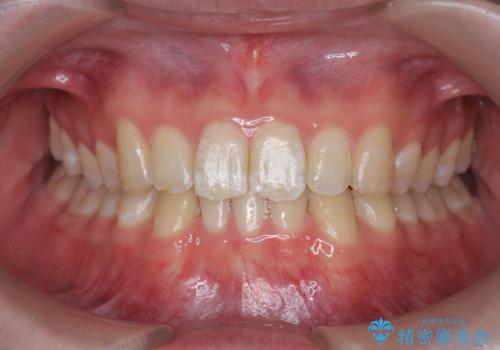

総合歯科治療 → 歯周病治療&矯正歯科治療

- 歯がボロボロで咬合崩壊 矯正・インプラント・セラミックで実現する、酸蝕症の総合治療- 担当医 河口智英